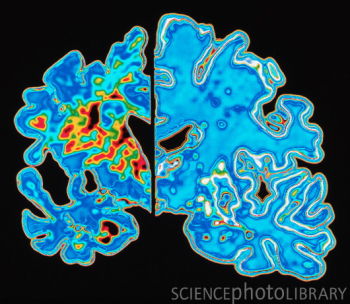

阿兹海默病(Alzheimer's disease,简称AD)又称老人痴呆症,全世界有2400万病患,是一种持续性神经功能障碍。疾病的成因未明,目前没有准确诊断和有效治疗的方法。阿兹海默病又称老年失智症,是失智症中最普遍的成因。最显著的早期症状为健忘,通常表现为逐渐增加的短期记忆缺失,而长期记忆则相对不受病情的影响。随着病情的加重,病人的语言能力,空间辨别能力,认知能力会逐步衰退。受AD影响的神经功能通常与大脑的额叶(frontal lobe)联系紧密,这反映了疾病的病理学过程。

阿兹海默病症状表现为逐渐严重的认知障碍(记忆障碍、见当识障害、学习障碍、注意障碍、空间认知机能、问题解决能力的障碍),逐渐不能适应社会。严重的情况下无法理解会话内容,无法解决如摄食,穿衣等简单的问题,最终瘫痪在床。